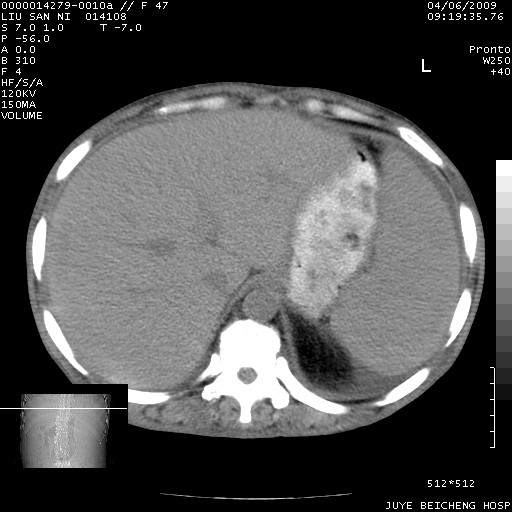

以下是引用前行在2009-4-7 10:31:00的发言:[br]肝脾肿大;双肾增大,双肾盂少量积水可能,肾膜膜增厚,肾周间隙增宽,并见桥间隔,提示结缔组系统疾病、系统性红瘢狼疮肾可能性大。继发右侧胸腔、心包、腹腔积液。

以下是引用深泽交通医院在2009-4-7 11:21:00的发言:[br]双侧肾周密度增高,见条索影,右肾实质见点片状低密度区,考虑弥漫肾炎【自身免疫性?】;;肾性水肿征